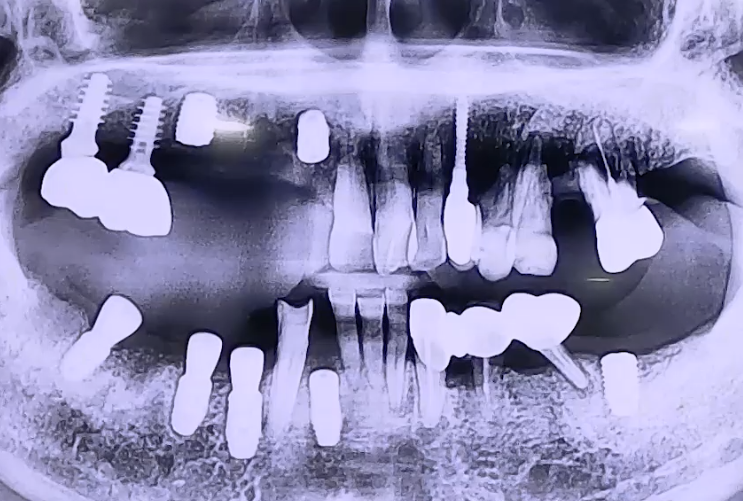

BEFORE

오른쪽 위아래 치아들의 극심한 통증으로 내원하신 환자분이십니다.

정밀검진 결과 풍치로 인해 치아들이 많이 흔들리며 통증이 발생한 것으로 확인되었는데요.

기존 치과에서 진행했던 임플란트들이 가늘고 긴 것으로 되어 있었는데,

이가 빠지고 시간이 지나 치아가 많이 기울고 공간이 부족해진 상태에서

임플란트 식립을 위해 이러한 선택을 해야 했던 것으로 보였습니다.

하지만 가느다란 임플란트가 어금니의 씹는 힘을 버티지 못해서

임플란트에도 함께 흔들림이 있으셨는데요.